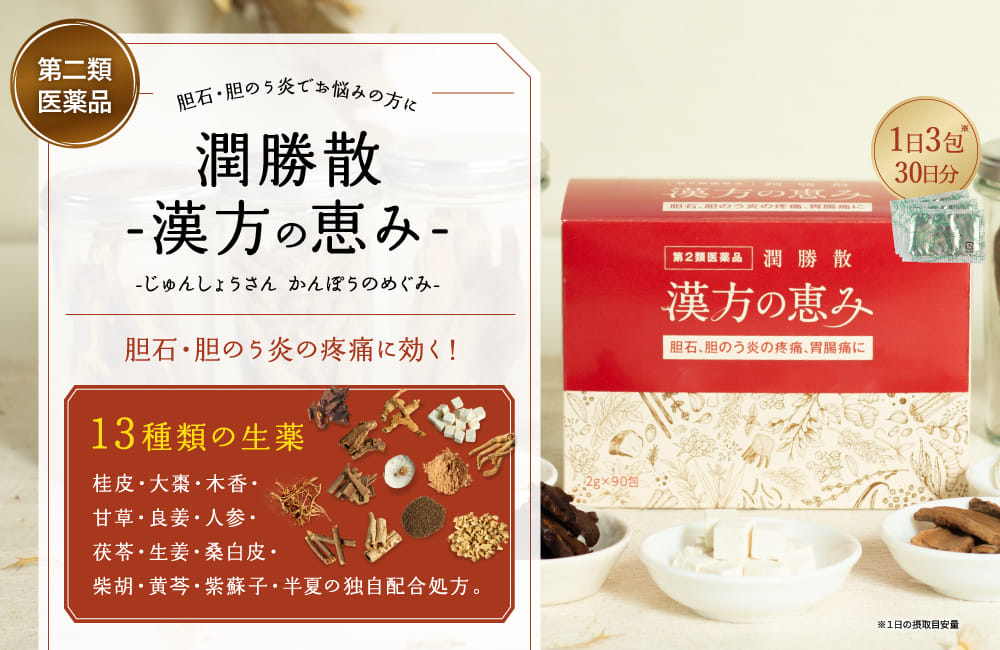

漢方薬“潤勝散”が

胆石⋅胆のう炎の

疼痛に効く!

13種類の生薬で独自配合された漢方薬※です。

※第二類医薬品

潤勝散 漢方の恵みは

胆石・胆のう炎の疼痛に

寄り添って考え作られた

「独自処方」の

漢方薬です。

潤勝散は13種類の生薬が胆石・胆のう炎の疼痛に

しっかりアプローチすることができる独自配合の漢方薬です。

- 内容量

- 2g×90包

- 効能・効果

- 胆石、胆のう炎の疼痛、胃腸痛、消化不良、食欲増進、腫気、肝臓病

- 成分・原料

- ケイヒ末/0.81g 、タイソウ末/0.24g、モッコウ末/0.24g、カンゾウ末/0.24g、リョウキョウ末/0.24g、ニンジン末/0.81g、ブクリョウ末/0.24g、 ショウキョウ末/0.81g、ソウハクヒ末/0.24g、サイコ末/0.81g、オウゴン末/0.24g、シソシ末/0.24g、ハンゲ末/0.81g 添加物は含有していません。